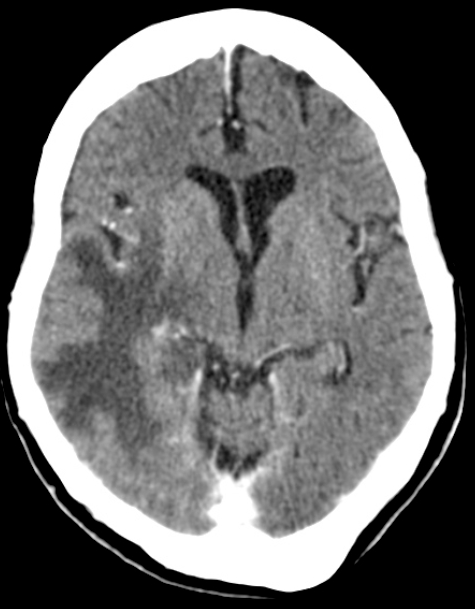

MRI나 CT에서 보이는 손가락 모양 (Finger-like projection)의 부종 양상이 바로 그 때문임.

6.주요 특징으로 백질(White matter)을 따라 국소적 또는 광범위하게 발생하며, CT는 저밀도(검게), MRI T2/FLAIR : 고신호(하얗게) 보임.